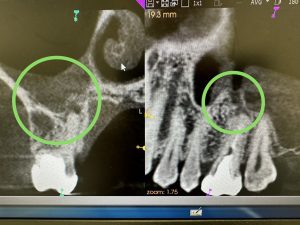

これも根管治療で治る、開かないMB1は根切併用かな

良くなりますよ!

今は、ヤグレーザーあるから、嫌われる外科処置しなくても3〰︎4カ月で骨化し咀嚼可能、後はMTAセメントやら自然治癒力で治ります

どちらが良いかは、もう少し吟味、比較検討する